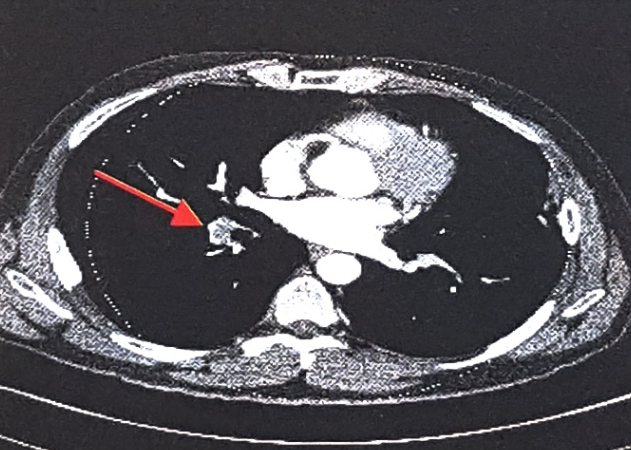

CT(Computed Tomography, 전산화단층촬영)검사는 신체의 일정 원하는 부위에서 단면을 깨끗한 2차원 영상으로 볼 수 있는 검사입니다. 촬영이 끝난 후 이러한 2차 단면영상을 컴퓨터를 이용하여 삼차원(3D)영상으로 재구성하면 동맥이 특별히 잘 보일 수 있도록 입체적인 영상도 얻을 수 있습니다.

CT촬영 종류에는 동맥 및 정맥 혈관 CT, 복부대동맥 CT, 심부정맥혈전 & 폐동맥 CT, 관상동맥 CT 등이 있습니다. 혈관질환의 정확한 검사 및 진단을 위해서는 혈관외과 전문의의 적절한 처방을 받아야 합니다.확인하고자 하는 대상에 따라서 촬영방법이 조금씩 차이가 있으나 기본적으로는 모두 같은 검사방법입니다.

심부정맥혈전증이 있거나 폐색전증이 의심될경우에 시행하는 검사로 매우 정확한 검사입니다.